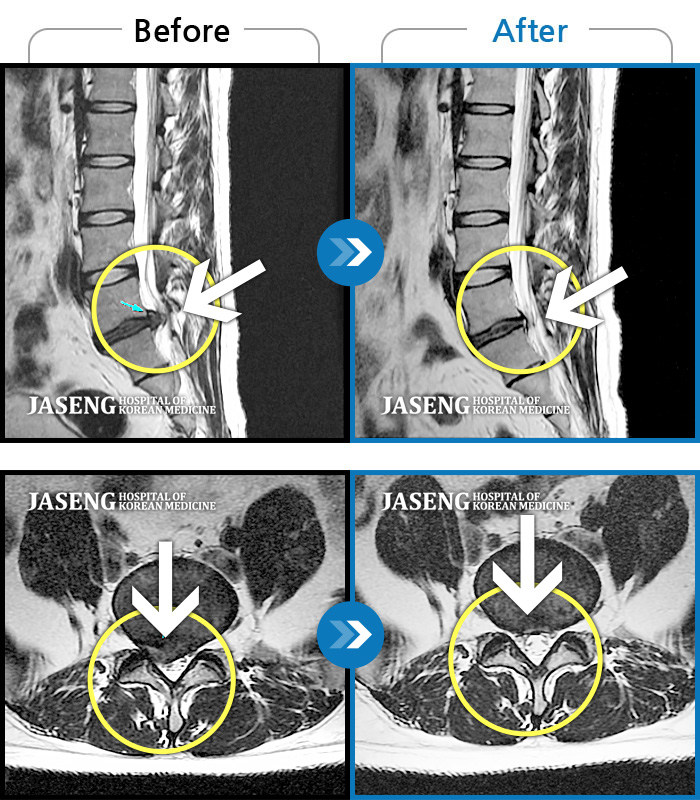

허리디스크

보라매 · 신원준 원장

허리통증과 우측 다리 저림이 심해서 앉거나 서기도 힘들어요

촬영시기

2023.08.01 ~ 2023.11.18

2023.12.08